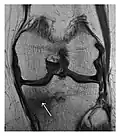

- a

- b

Figure 9: Proximal metaphyseal fatigue fracture of the tibia in a 27-year-old recent male military recruit. (a) Anteroposterior radiograph is within normal limits. (b) Coronal T1-weighted MR image shows a marked linear hypoattenuation along the medial tibial metaphysis (arrow) surrounded by diffuse hypointensity in keeping with posttraumatic edema.[1]